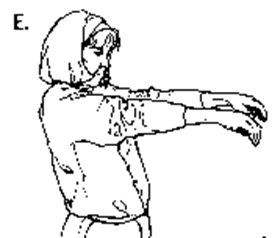

E. Straighten both wrists and relax fingers, for a count of 5.

F. The exercise should be repeated 10 times. Then let your arms hang loosely at the side and shake them for a few seconds.